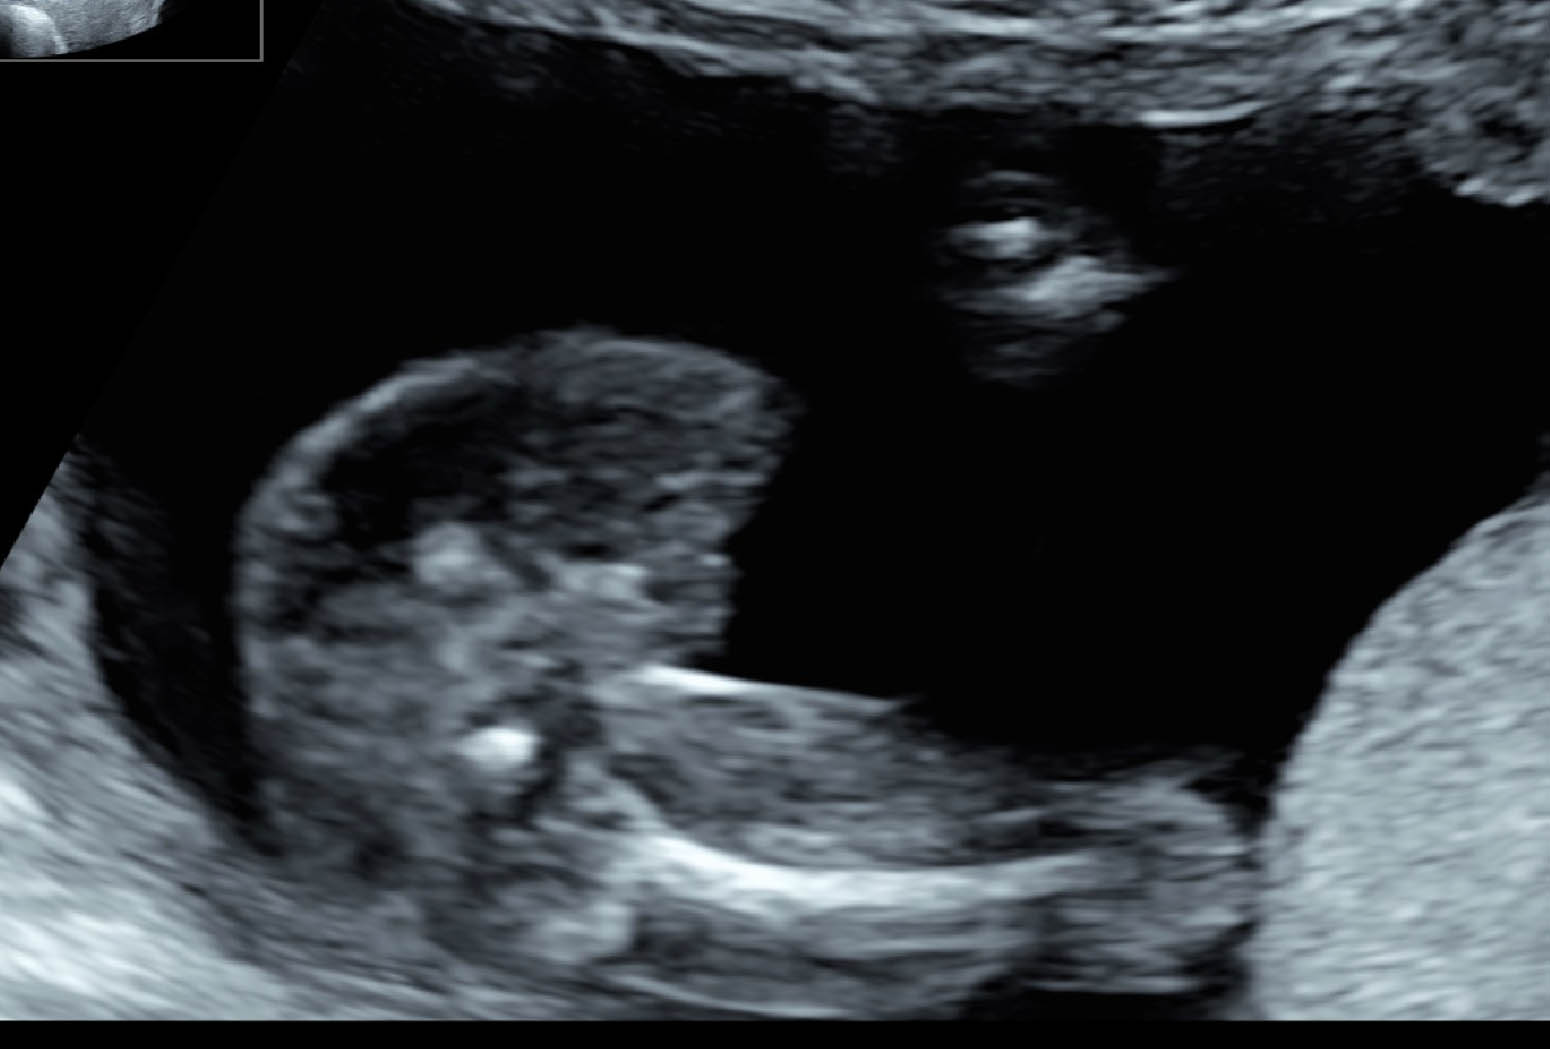

This is my baby's ultrasound at 17 weeks. The doctor didn't want to reveal the gender yet (said she's not 100% sure). I don't know if these are good gender shots, but what would you say?